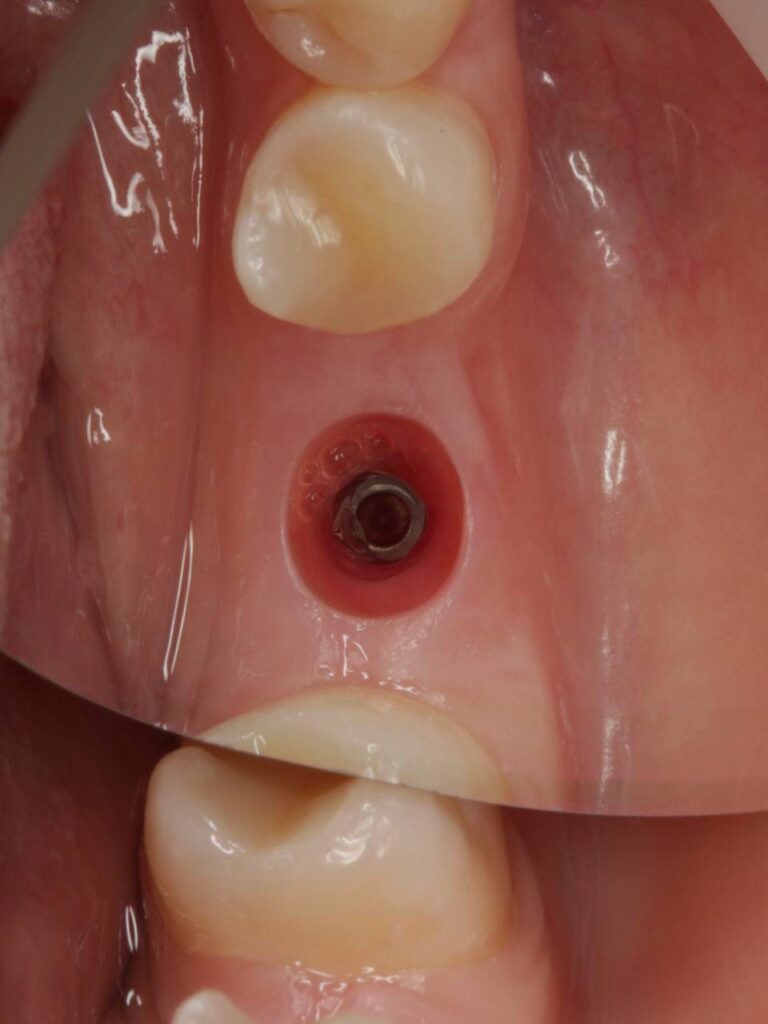

Специализация: терапия(эндодонтия), ортопедия, имплантология.